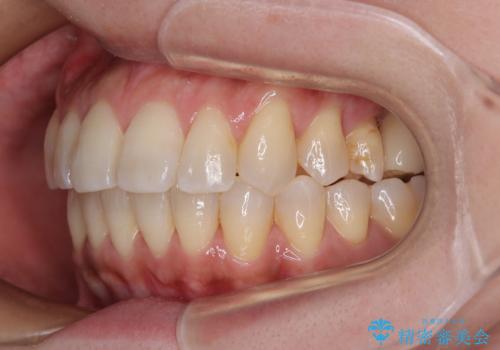

歯の傾斜が改善され、インプラントによるクラウンが装着されたことで、物が挟まることもなくなりました。